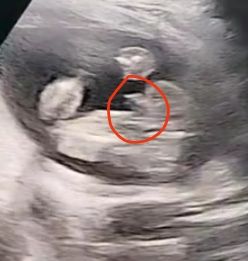

Как делаете точно мальчик?

Мальчуган

450 гр мальчик ) писюн так же показывали )

Да мальчик😃нам тоже на втором скрининге показали такой писюн)вес был 331 гр,было 20 недель, 4 дня